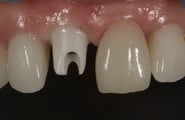

抜歯した直後にインプラントを埋入し、仮の歯を作製、唇側の骨のボリュームを保つために人工骨と結合組織を同時に移植する非常に優れた方法です。

しかし、非常に難易度の高い手術になります。